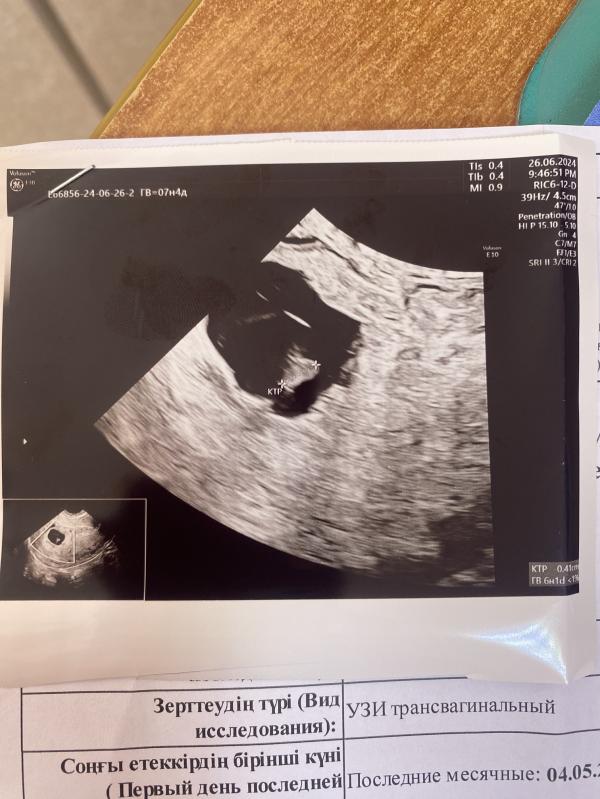

Пришла на плановое узи в почти 7 недель слушать сердцебиение. У меня ЭКО. Все анализы по расписанию. Первое - кровь на хгч на 10 день подсадки - 325. Второе - узи через неделю для определения плодного яйца - все есть. Третье - через 2 недели узи на сердцебиение. …а его нет…меня как током прошибло. Почувствовала как волосы на голове встали дыбом. «Как это возможно, все же хорошо, как это можно не чувствовать» и слезы градом…..не легко узи там сообщать такие новости. Меня отправили сразу в больницу. Но репродуктолог сказал подождать еще неделю и ничего не делать. Но я в чудеса не верю. Ни на какую позднюю овуляцию тут не сослаться. Я ждать не стала. Сделала хгч в динамике. 20 000 ед. Через 2 дня - уже 17 000. Отправляю репродуктологу, а он мне говорит что такое бывает на таких сроках. «Не мой случай»думаю я. У меня все должно быть четко, как по линейке. В общем. Чуда не случилось. Повторное узи - нет сердцебиения и эмбриончик еще уменьшился. Я даже не плакала уже. За неделю ношения замершей беременности я успокоилась. Благо есть старший ребенок, ему 2 года. Он не дает впадать в отчаяние.